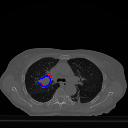

However, in a few rogue cases, where the shapes of the ground truth are exceedingly uncoordinated, perhaps with fissures in the middle or with erratic outlines, it is seen that the predicted tumor regions are prone to imperfections. Although for these cases, our model can predict the existence of tumors, the shapes can often appear to have disfigurements. This is demonstrated in Figure 6. We plan on addressing this issue in our future work.